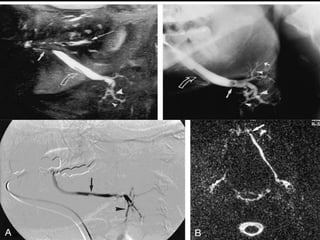

£. Conventional sialography

using panoramic occlusal, and panoramic

radiography is useful in cases where there

is a strong clinical suspicion of

inflammation or salivary stone disease

contrast sialography using iodinated

contrast media may be used to visualize

the parotid and submandibular ductal

system

Limitation

o use of ionizing radiation

o dependence on successful ductal

cannulation

o pain during and after the procedure

o potential allergy to the contrast media

Contra indicated in presence of acute

sialadenitis.

£. Conventional sialography usingpanoramic occlusal, and panoramic radiography is useful in cases where there is a strong clinical suspicion of inflammation or salivary stone disease

contrast sialography usingiodinated contrast media may be used to visualize the parotid and submandibular ductal system

Limitation o use ofionizing radiation o dependence on successful ductal cannulation o pain during and after the procedure o potential allergy to the contrast media Contra indicated in presence of acute sialadenitis.